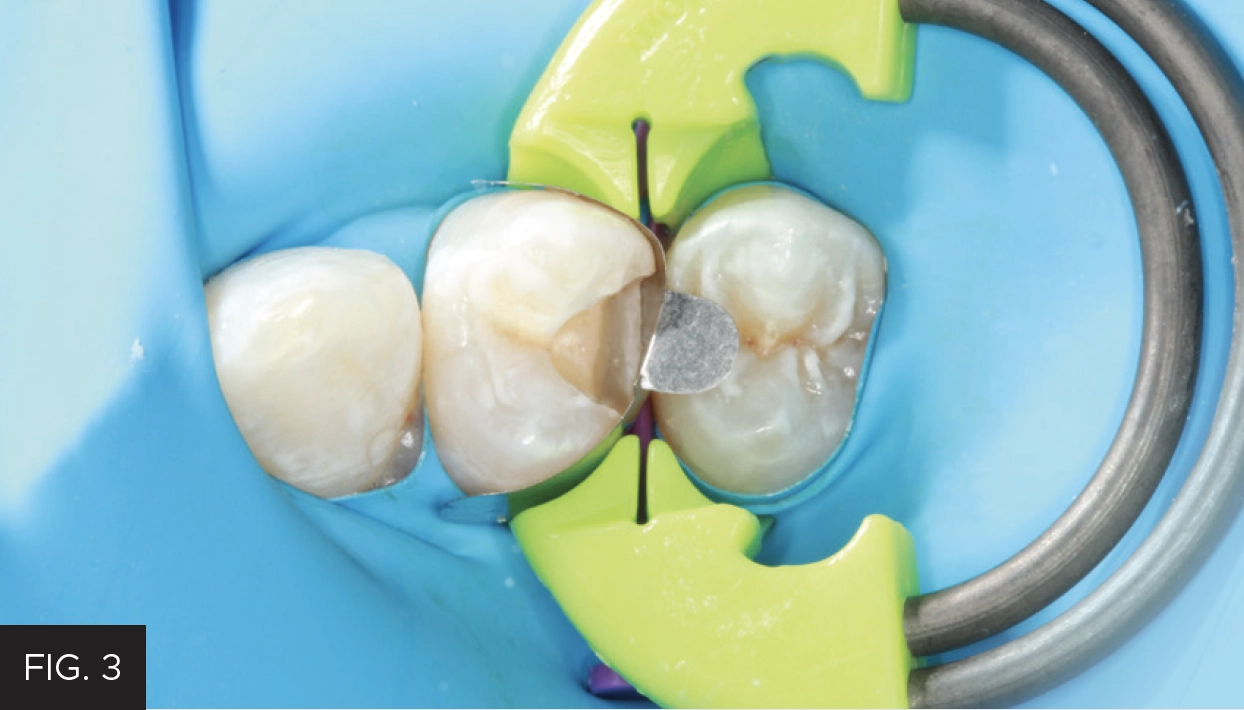

In addition to the superior design of the DualForce Ultra-Wrap Matrix Bands and the DualForce Active-Wedges, the DualForce™ Ring is the final component in this system to ensure the proper isolation and seal for the restoration. (FIG. 3) The DualForce System has a smaller orange pre-molar ring and a larger green molar ring. The use of one or the other is at the clinician’s discretion, taking into account the degree of access and the use of multiple rings simultaneously. The DualForce Ring Forceps were positioned into the DualForce Ring engagement slots and the ring was placed over the wedge, engaging the DualForce Ultra-Wrap Matrix Band. Then, visual confirmation was used to see that the DualForce Ring sat at a 20-degree angle to the occlusal plane. This design is twofold: it creates maximum separation interproximally and prevents interference with the adjacent rubber dam clamp. If needed, slight finge pressure is applied on the plastic tines to fully seat the ring, as any pressure on the NiTi rings may dislodge the ring.

The DualForce Sectional Matrix System by Clinician’s Choice. Its innovatively designed components include the DualForce Ultra-Wrap Matrix Band, the DualForce Active-Wedge, and the DualForce Ring.